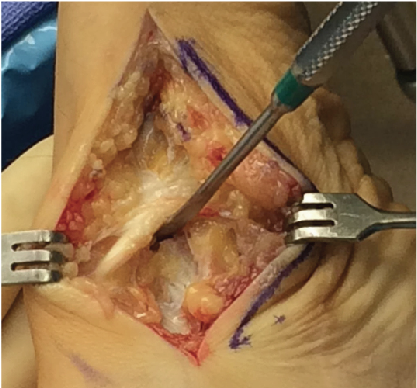

For the approach to the medial column, one makes a medial midfoot incision originating anterior to the medial malleolus and extending to the first tarsometatarsal joint. Keep the incision below the medial venous structures to allow them to be easily retracted. Once there is adequate exposure, identify and retract the saphenous nerve with the venous vessels. In some patients, the medial origin of the naviculocuneiform joint may appear unclear and an easy guide is the insertion of the tibialis anterior tendon onto the medial cuneiform. The tibialis anterior tendon forms a firm veil to the medial naviculocuneiform joint and mobilization immediately proximal to the insertion with elevation of the tendon exposes the joint.

Sharp release of the ligamentous structures dorsally and plantarly allows for enough exposure to see the first 5 mm of the medial cuneiform to allow for appropriate preparation of the resection of the joint. I am careful to avoid over-aggressive resection of the joint surfaces. Starting the resection too proximal on the navicular and/or too distal on the cuneiform may result in overcorrection of the foot. Performing a minimal initial resection allows for more aggressive resection or planing later if necessary. I attempt to remove 2 to 3 mm of cartilage, which includes both the articular cartilage and the calcified cartilage layer. One performs this resection on both sides of the joint, including the first and second cuneiform, and, if necessary, the third cuneiform. I do not believe an isolated first cuneiform-navicular fusion is adequate to provide a solid construct for fusion of the entire three-joint complex.8 When one performs an isolated medial cuneiform navicular fusion, there is less than 50 percent of the joint surface fused and the majority of the joint maintains motion, directly working against the goal of a solid fusion site.

Once you have exposed the cancellous bone of the fusion site, place a self-retaining bone retractor into the surgical site and prepare the joints for fusion with subchondral drilling and fish scaling. One can accomplish fusion reduction with a bone reduction forceps. Prior to placing hardware, evaluate the alignment of the foot. Ideally, the first ray should be parallel to the lesser rays and the heel bisection should exit through the second ray. Evaluate the fusion site for gapping and close apposition. If the dorsal margins of the fusion site have been inadequately resected, the presence of a bony bridge can prevent clear apposition, which requires feathering with a sagittal saw or bony resection.

One can achieve fixation of the fusion with screws, plates (locking and non-locking) or staples. I commonly perform internal fixation with cannulated screws. Once I am confident in the alignment and temporary position of the fusion, I will place my guide wires. I will place three screws and the anatomy dictates whether it is two screws proximal and one screw distal or one screw proximal and two screws distal. The surgeons should place all these screws below the midline vertical bisection of the joint. The first screw I place is from the medial cuneiform to the lateral pole of the navicular. I am aiming from the distal-plantar medial cuneiform to the anterior process of the calcaneus. Place the second screw from the navicular to the lateral cuneiform and aim the guide wire from the inferior navicular tuberosity to the central fifth metatarsal. The last screw is distal or proximal depending on the available anatomy. I commonly place my third screw from the navicular to the intermediate cuneiform.